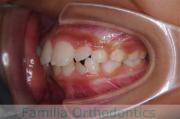

前歯の関係など

右側

正面

左側